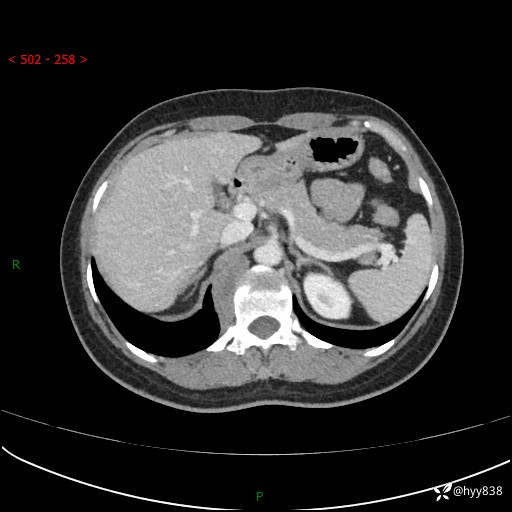

现在都流行跨界,病变也不例外,从腹膜后长到胸腔了---结果公布~

主诉:体检发现右侧腹膜后肿物1天

简要病史:患者于1天前因体检发现右旁肾占位,无肉眼血尿,无畏寒发热,无咳嗽咳痰,无腰腹部疼痛不适,无尿频尿急症状,起病来,患者未行特殊治疗,为求进一步诊治,门诊以"右侧腹膜后肿物"收治入院。 发病来患者精神、饮食、睡眠良好,小便如上,大便正常,体重无明显变化。

临床诊断:腹膜后肿物

上腹部CT增强(动脉期+实质期)(外院平扫)